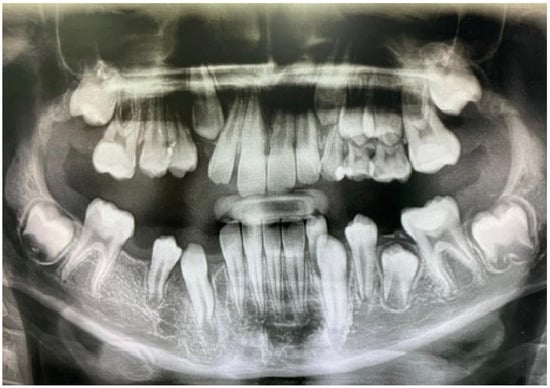

The orthopantomogram, brought by the patient, presented unycistic radiolucency with well-defined margins on the mandible’s right side as well as the left side of the maxilla. A multi-slice computed tomogram (MSCT) showed a cystic lesion in the maxilla extending from the second left permanent incisor to the first permanent molar. It included the unerupted follicles of the permanent canine, first, and second premolar, and was separated from the maxillary sinus by a thin bone. A second lesion was observed in the mandible, extending from the primary right canine to the first permanent molar. It also involved the crowns of the unerupted permanent teeth [Figure 5a,b].

Figure 5. Preoperative MSCT of a nine-year-old boy showing unicystic radiolucencies on the right side of the mandible (a) and left side of the maxilla (b).

The same procedure was performed as in the first case, in which the first and second upper and lower deciduous molars were extracted. A biopsy was taken at both sites, and the same decompression devices were placed in the extraction sockets. The patient was advised to irrigate the cyst cavities with saline [Figure 6]. Histopathologic analysis of the lesions confirmed the diagnosis of dentigerous cysts, characterized by lining of 2–4 layers of non-keratinized epithelium and infiltration of inflammatory cells within the fibrous wall. Postoperative radiographs showed a gradual reduction of the lesions, and all permanent teeth erupted after one year [Figure 7]. No recurrence of the lesions was noted on a three-year follow-up radiograph [Figure 8]. The patient was referred to an orthodontist for the correction of occlusion.

Figure 7. Twelve-month postoperative panoramic radiograph showing the resolution of both lesions.

Figure 8. A three-year follow-up panoramic radiograph showing no recurrence of the lesions.